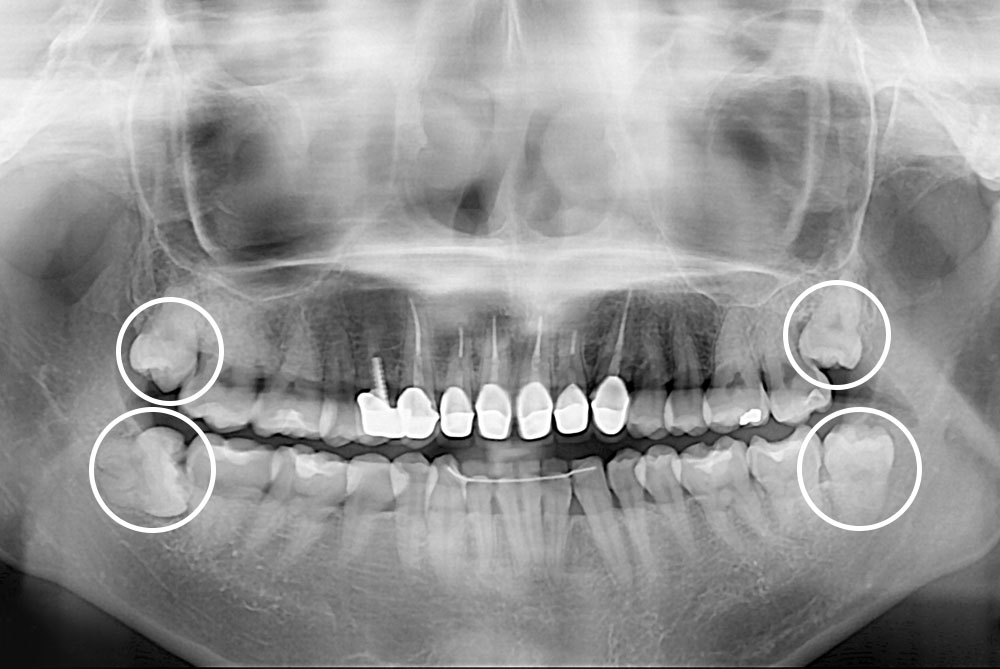

[사랑니] 매복 사랑니 발치

치료전 : 2019-08-30